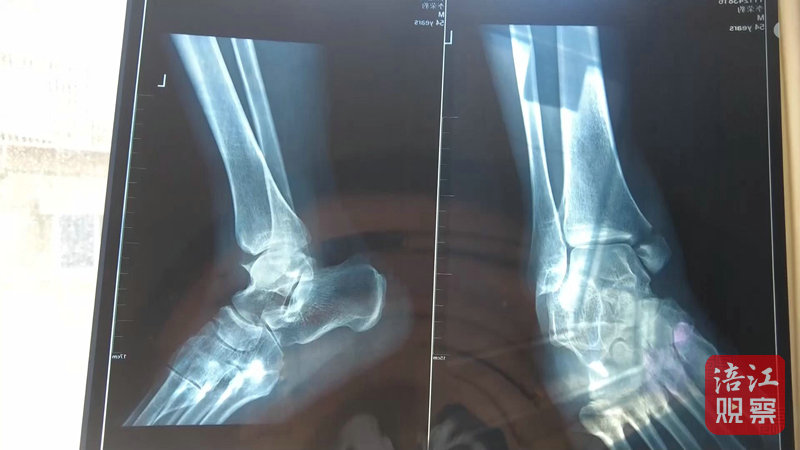

4月22日,記者來到綿陽市骨科醫(yī)院,病房?jī)?nèi),李先生正在進(jìn)行術(shù)后上下床的康復(fù)訓(xùn)練。李先生的主治醫(yī)生介紹,李先生因左內(nèi)踝骨折入院,手術(shù)一周后傷口愈合良好,病情穩(wěn)定,目前已轉(zhuǎn)入康復(fù)科進(jìn)行康復(fù)功能鍛煉。